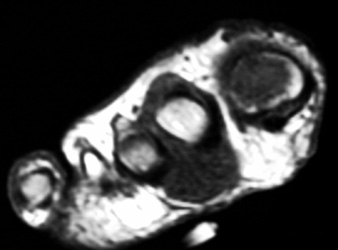

MR appearance: Typically present as persistent intermediate to low signal intensity on T1W and T2W with surrounding inflammation and post contrast enhancement. Bony erosions are also seen well.

44years old male with rapidly enlarging mass in the foot. Radiographs demonstrates soft tissue mass between the 2nd and 3rd toes,with no calcification.Well defined erosion is noted at the radial aspect of the base of proximal phalanx of 2nd toe. Mild soft tissue swelling with faint calcification is also seen at 1st MTP joint ,with small erosion medial aspect of 1st Mt head. MR demonstrates mass is isointense to hypointense on T1W, and T2W images, with minimum bone marrow edema at the base of proximal phalanx of 2nd toe. Erosion is well seen at the base of proximal phalanx of 2nd toe on T1W images.